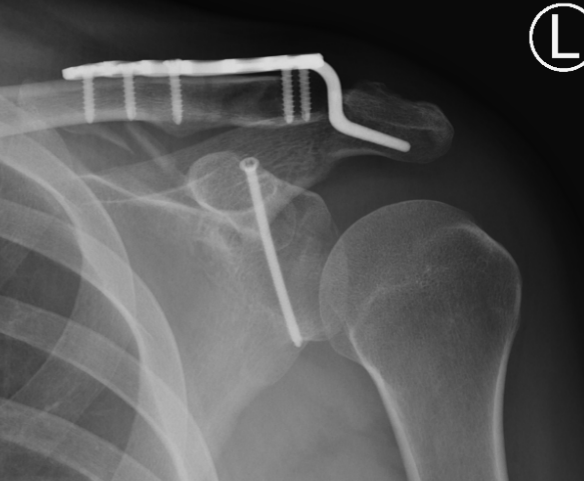

Type IA: Anterior glenoid rim fracture

Xray / CT